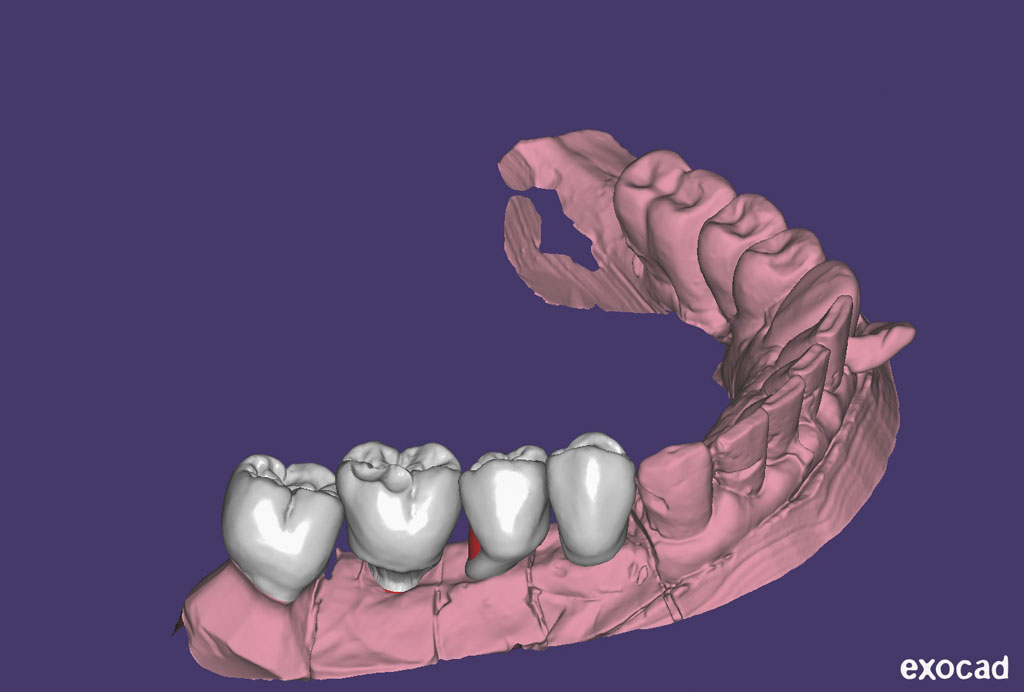

Fehlen in der Front oder im Seitenzahnbereich mehrere Zähne, ist eine Brücke oder Prothese vollkommen unnötig. Die fehlenden Zähne können entweder einzeln durch eine entsprechende Anzahl von Implantaten oder durch implantatgetragene festsitzende Brücken ersetzt werden. Das Bild der Kronen zeigt die drei Verschraubungen deutlich, im Mund liegen diese verdeckt am Gaumen oder im Bereich der Zunge.